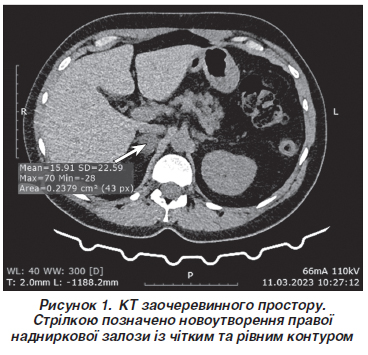

Наведено клінічний випадок запізнілого діагнозу первинного гіперальдостеронізму (ПГА) внаслідок альдостеронпродукуючої аденоми (АПА). Підозра на ПГА виникає у випадку стійкого поєднання артеріальної гіпертензії (АГ) з гіпокаліємією різного ступеня вираженості, специфічним нейром’язовим синдромом, а також не властивих для банальної АГ високого ризику кардіоміопатії, серцевої недостатності, погіршення функції нирок. Імовірність ПГА підвищує факт незадовільного контролю артеріального тиску стандартною комбінацією засобів фармакотерапії, неочікуваний позитивний ефект антагоністів мінералокортикоїдних рецепторів, АГ у молодих, а також сімейний анамнез ранньої АГ або інсульту у молодому віці, пароксизмальний перебіг власне АГ. Тривалий час захворювання нашої пацієнтки розцінювали як банальну гіпертонічну хворобу, хоча діагностична гіпотеза ПГА повинна була з’явитися одразу після початку домінування у клінічній картині тяжкого нейром’язового синдрому, швидкого прогресування кардіоміопатії та клінічно значущої серцевої недостатності. 44-річна пацієнтка опинилася у полі зору фахівців-ревматологів з підозрою на запальну міопатію через часті епізоди м’язової слабкості, походження якої залишалося нез’ясованим. Ключові скарги на пароксизмальну виражену генералізовану м’язову слабкість, особливо кінцівок, оніміння і парестезії у кінцівках, судоми м’язів гомілок на фоні АГ було сприйнято як специфічний для ПГА нейром’язовий синдром. Гіпотеза ПГА підкріплювалася наявністю кардіоміопатії, серцевої недостатності, клінічно значущої гіпокаліємії та підвищеного рівня альдостерону. Комп’ютерна томографія заочеревинного простору підтвердила наявність аденоми наднирника. На жаль, із запізненням, через 13 років існування АГ, було констатовано діагноз ПГА на фоні АПА. Запропонована консультація хірурга-ендокринолога, а також еплеренон 50 мг на добу у поєднанні із лерканідипіном 20 мг на добу. Вже через 6 тижнів фармакотерапії отримано позитивний терапевтичний ефект щодо контролю АГ, серцевої недостатності та вираженості нейром’язового синдрому. Диференціальна діагностика вторинної ендокринної АГ може бути успішною лише за умови володіння навичками раннього клінічного розпізнавання патології ендокринної системи, навіть при субклінічному перебігу хвороби. Констатація ПГА дозволяє пропонувати пацієнту радикальне хірургічне лікування, а також обрати оптимальні підходи до фармакотерапії.

A clinical case is presented of delayed diagnosis of primary hyperaldosteronism (PHA) due to aldosterone-producing adenoma. Suspicion of PHA arises in case of persistent combination of hypertension with hypokalemia of various severity, a specific neuromuscular syndrome, as well as a high risk of cardiomyopathy, heart failure, and deterioration of kidney function, which are not typical for banal hypertension. Unsatisfactory blood pressure control with a standard combination of pharmacotherapy, an unexpected positive effect of mineralocorticoid receptor antagonists, high blood pressure in young people, as well as a family history of early high blood pressure or stroke at a young age, paroxysmal course of hypertension itself increases the risk of PHA. For a long time, a disease in our patient was considered a banal hypertension, although the diagnostic hypothesis of PHA should appear immediately after severe neuromuscular syndrome, rapid progression of cardiomyopathy and clinically significant heart failure began to dominate in the clinical picture. A 44-year-old female patient came to the attention of rheumatologists with suspicion of inflammatory myopathy due to frequent episodes of muscle weakness whose origin remained unclear. Key complaints of pronounced paroxysmal generalized muscle weakness, especially in the limbs, numbness and paresthesias in the extremities, calf muscle cramps against the background of hypertension were regarded as a neuromuscular syndrome specific to PHA. The PHA hypothesis was supported by the presence of cardiomyopathy, heart failure, clinically significant hypokalemia, and elevated aldosterone level. Computed tomography of the retroperitoneal space confirmed the presence of adrenal adenoma. Unfortunately, with a delay, after 13 years of hypertension, the diagnosis of PHA against the background of aldosterone-producing adenoma was confirmed. Consultation with a surgeon endocrinologist was suggested, as well as administration of eplerenone 50 mg daily in combination with lercanidipine 20 mg daily. Already after 6 weeks of pharmacotherapy, a positive therapeutic effect was obtained regarding the control of hypertension, heart failure, and the severity of neuromuscular syndrome. The differential diagnosis of secondary endocrine hypertension can be successful only with the possession of skills for early clinical detection of endocrine pathology, even in subclinical disease presentation. The diagnosis of PHA makes it possible to offer a patient radical surgical treatment, as well as to choose optimal approaches to pharmacotherapy.